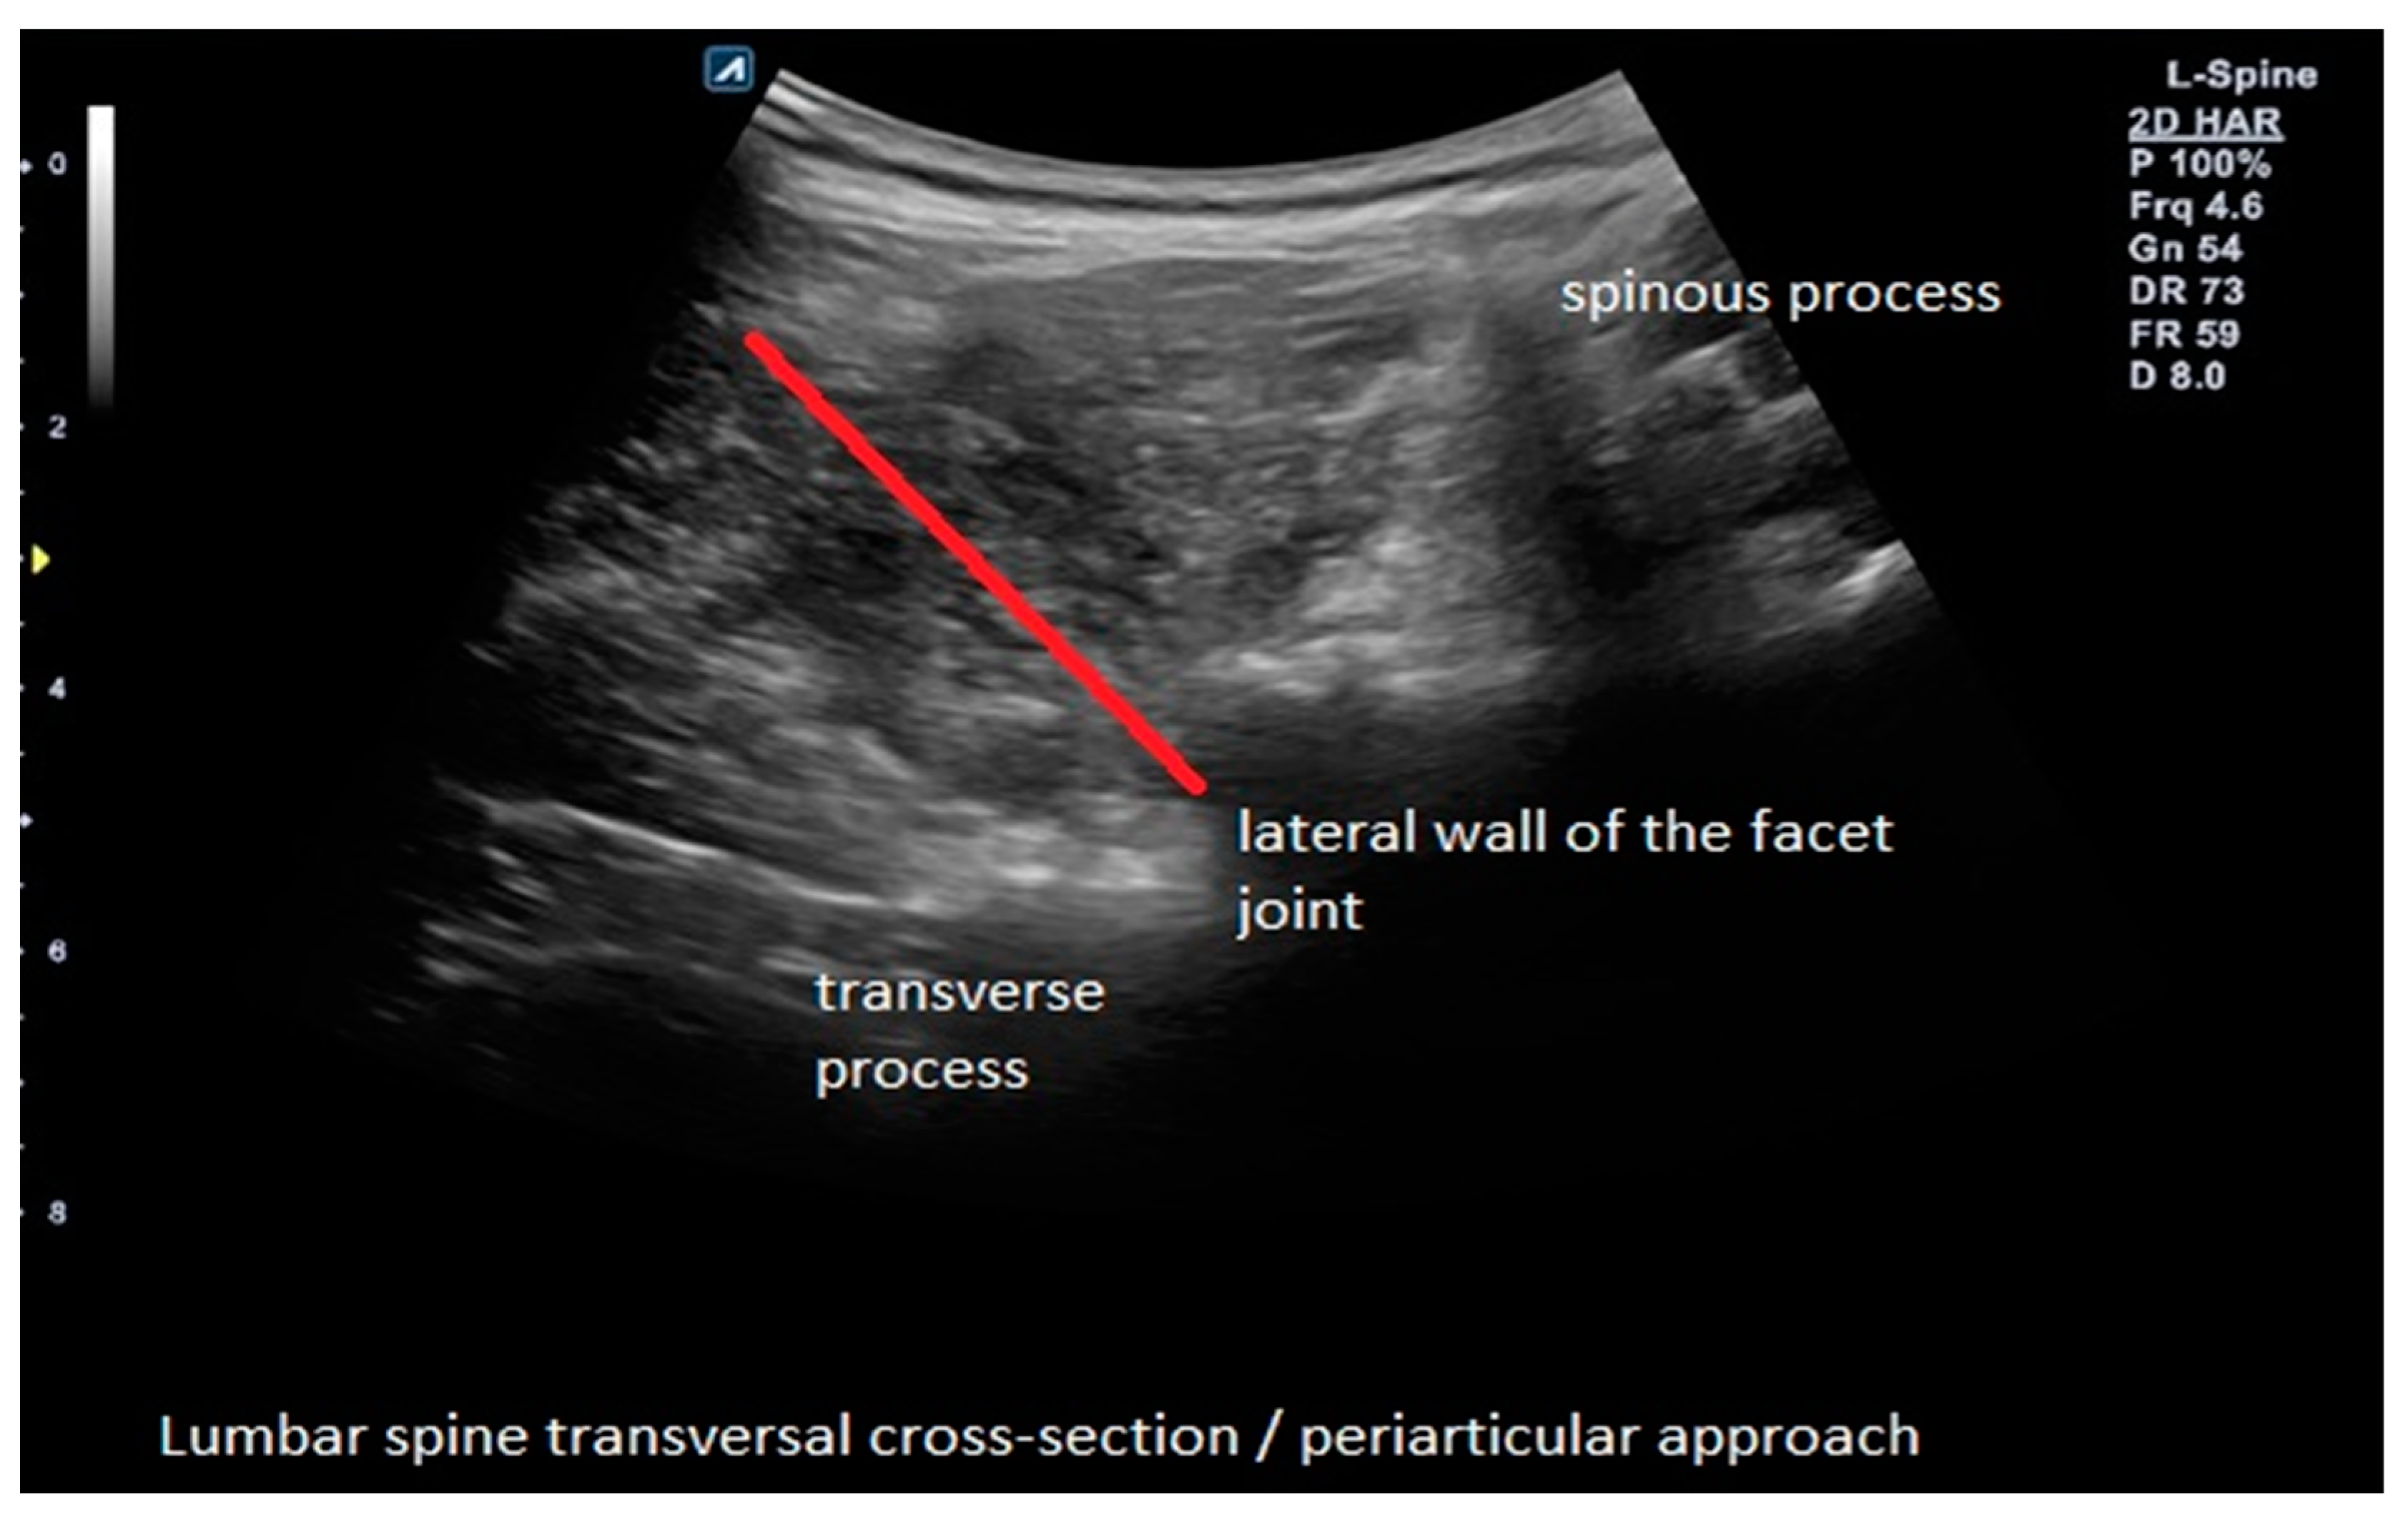

The experimental group (B) received an ultrasound-guided perineural (periarticular) injection where the needle is guided upon the lateral wall of the articular process (as it is performed in the medial branch block) so that the injectate is spread indirectly over the nerve root, which it is not the same as a transforaminal approach because ACS is localized around facet joints of the affected segment (Figure 1).

Figure 1.

Example of ultrasound-guided perineural (periarticular) ACS injection with needle trajectory in the experimental group (B).